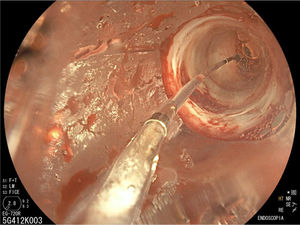

La endoscopia reveló un estrechamiento del píloro que impedía el paso del endoscopio al duodeno (fig. 1), por lo que se realizó dilatación hidroneumática con balón (figs. 2 y 3). Las biopsias informaron gastritis asociada a Helicobacter pylori e hiperplasia foveolar.